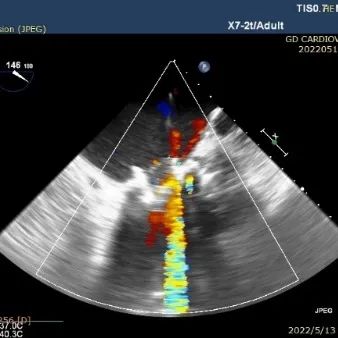

术中TEE&DSA影像:

二尖瓣位人工生物瓣中度狭窄

二尖瓣位人工生物瓣重度关闭不全